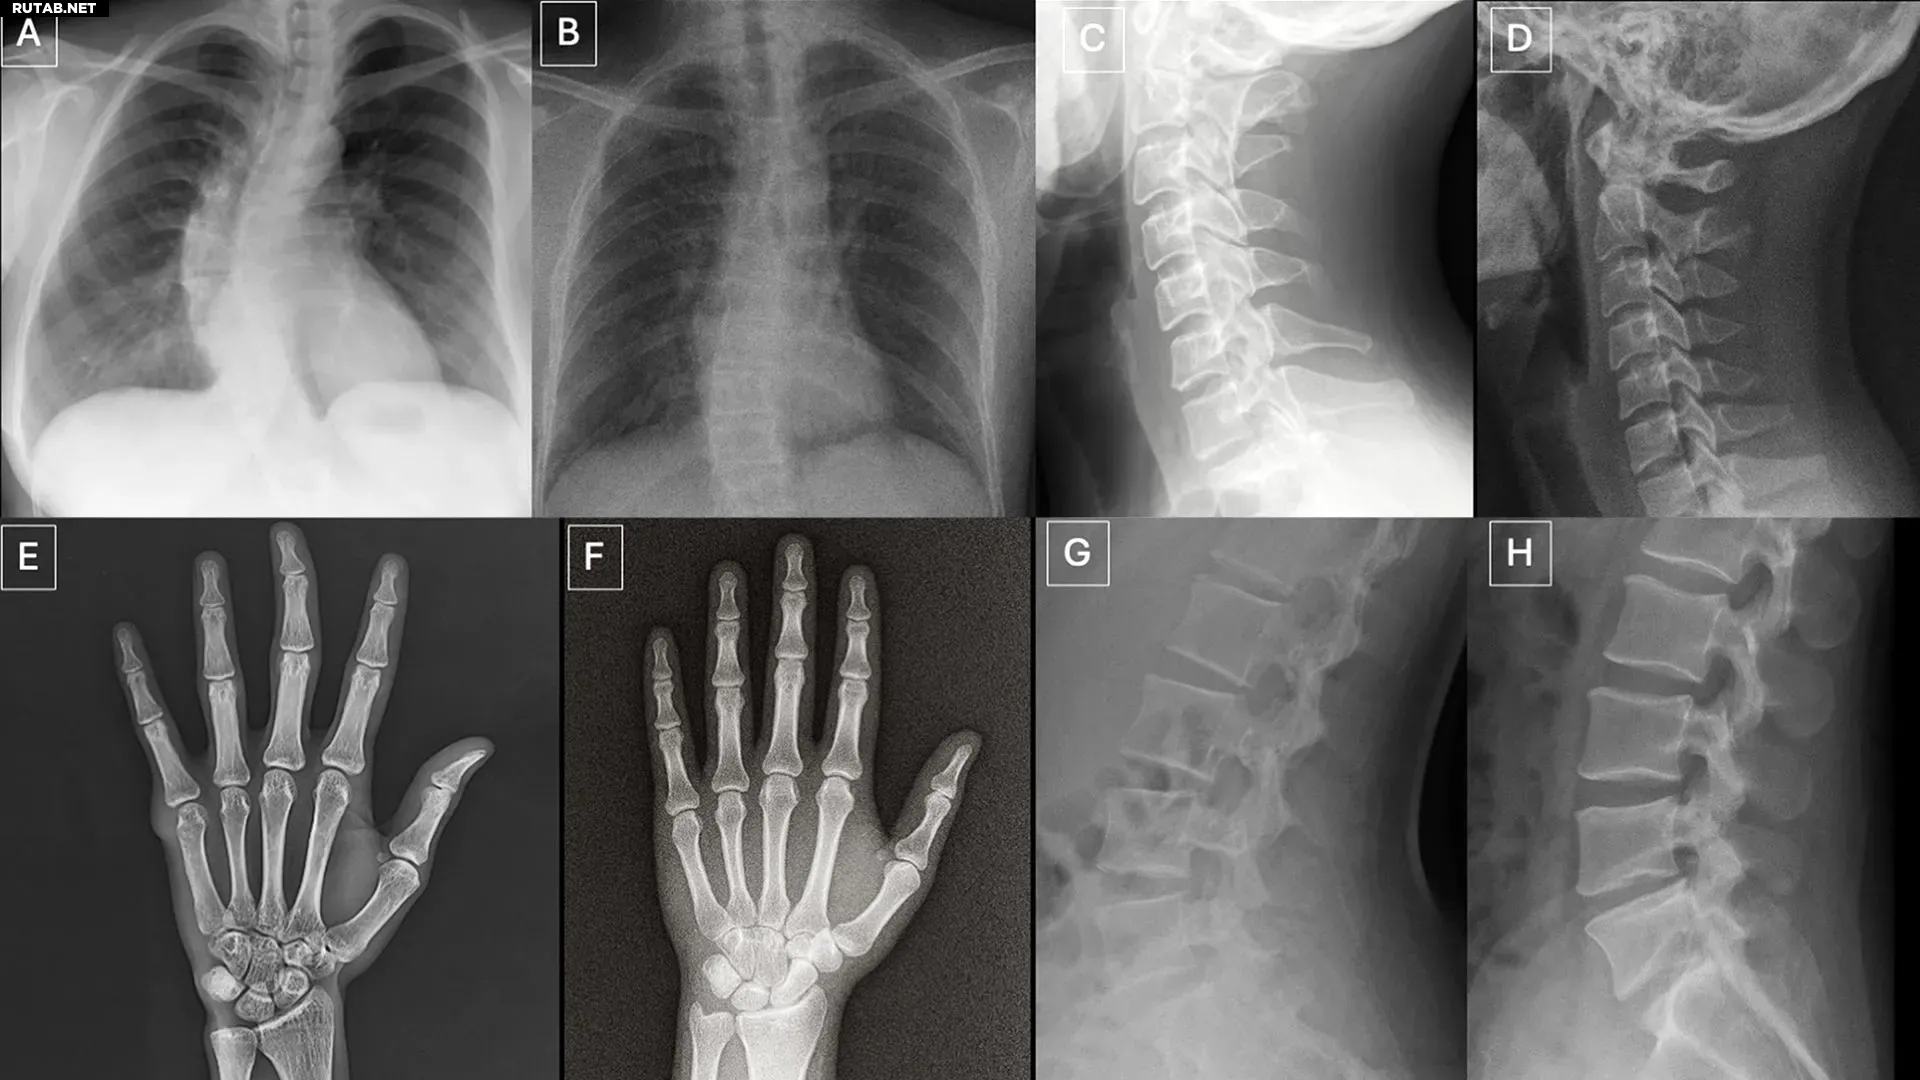

Искусственные рентгеновские снимки от ИИ обманывают даже опытных врачей

Новое исследование, опубликованное в журнале Radiology, показало, что как рентгенологи, так и современные мультимодальные языковые модели (LLM) с трудом отличают настоящие рентгеновские снимки от сгенерированных искусственным интеллектом «дипфейков». Это создаёт серьёзные риски для медицины.

Исследователи отметили, что сгенерированные изображения часто выглядят «слишком идеально»: кости чрезмерно гладкие, позвоночник неестественно прямой, а переломы — необычно «чистыми».